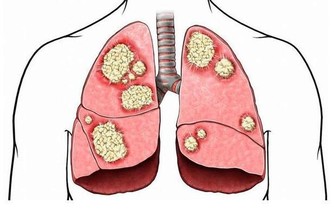

三:護肺番茄

最新研究發現,每星期吃番茄3次以上可以預防呼吸系統疾病,保護雙肺免受細菌的感染。

但番茄紅素的含量與番茄中可溶性糖的含量是成反比的,

也就是說,越是不甜的西紅柿,其中番茄紅素含量越高。